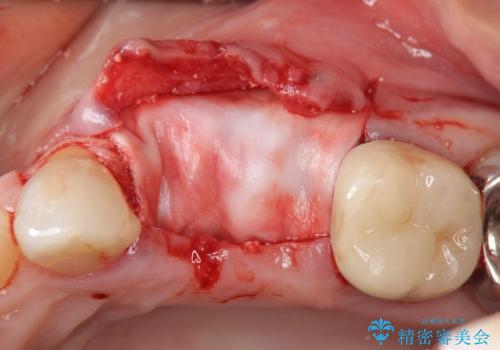

歯の穿孔(内部穴が開いている状態)破折等、歯を保存することができない問題が小臼歯には認められたので抜去を行います。

抜去後の補綴治療は長いブリッジではなくインプラント治療を希望されましたが、穿孔・破折による周囲の骨吸収をリカバリーすべく骨の造成を伴うインプラント治療を計画します。

インプラント治療を行うにはインプラント周囲に十分な骨の幅・高さが必要です。

今回はが原因で失われてしまった骨の幅を回復することで長期的な予後を見込めるインプラント治療を行うことができました。